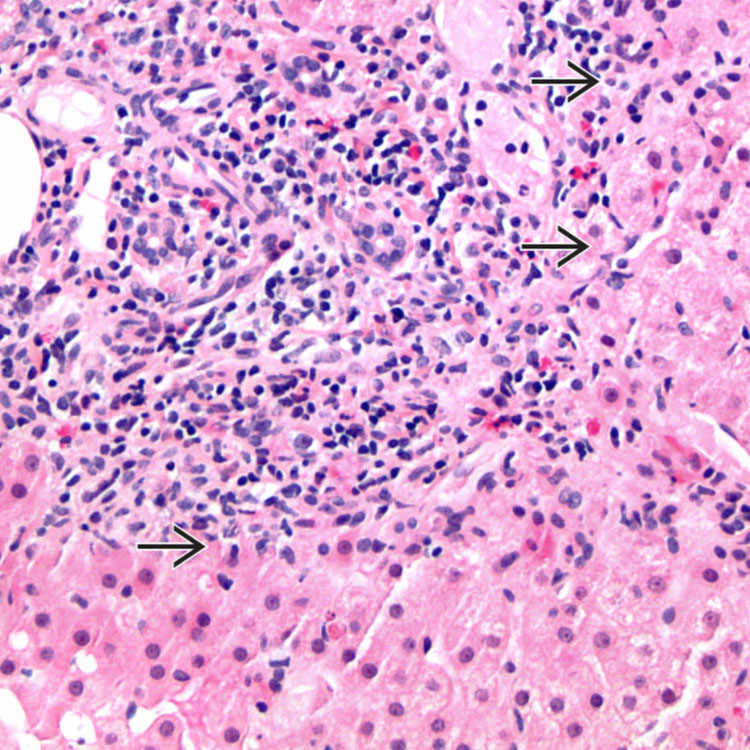

Interface Hepatitis Pathology Outlines . Simple system evaluating 4 laboratory and histological factors: Expanded portal regions with dull edges suggestive of interface hepatitis (ul 40x). Interface activity is readily identified and is considered a characteristic feature of aih; Aih is also considered likely if there is predominantly lobular hepatitis with or without centrilobular necroinflammation and at least one. This review describes pathologic and clinical features of a spectrum of hepatitic liver disease that can cause chronic hepatitis, as well. Pas without diastase shows interface hepatitis. Prominent chronic inflammatory infiltrate with occasional germinal centers in portal tracts with variable. This broad topic highlights the pathophysiology, microscopic findings and associated hepatic diseases with commonly. Simplified criteria for diagnosis of autoimmune hepatitis are based on autoantibodies, serum immunoglobulin g,. Serum autoantibodies, igg, liver histology and viral hepatitis serology.